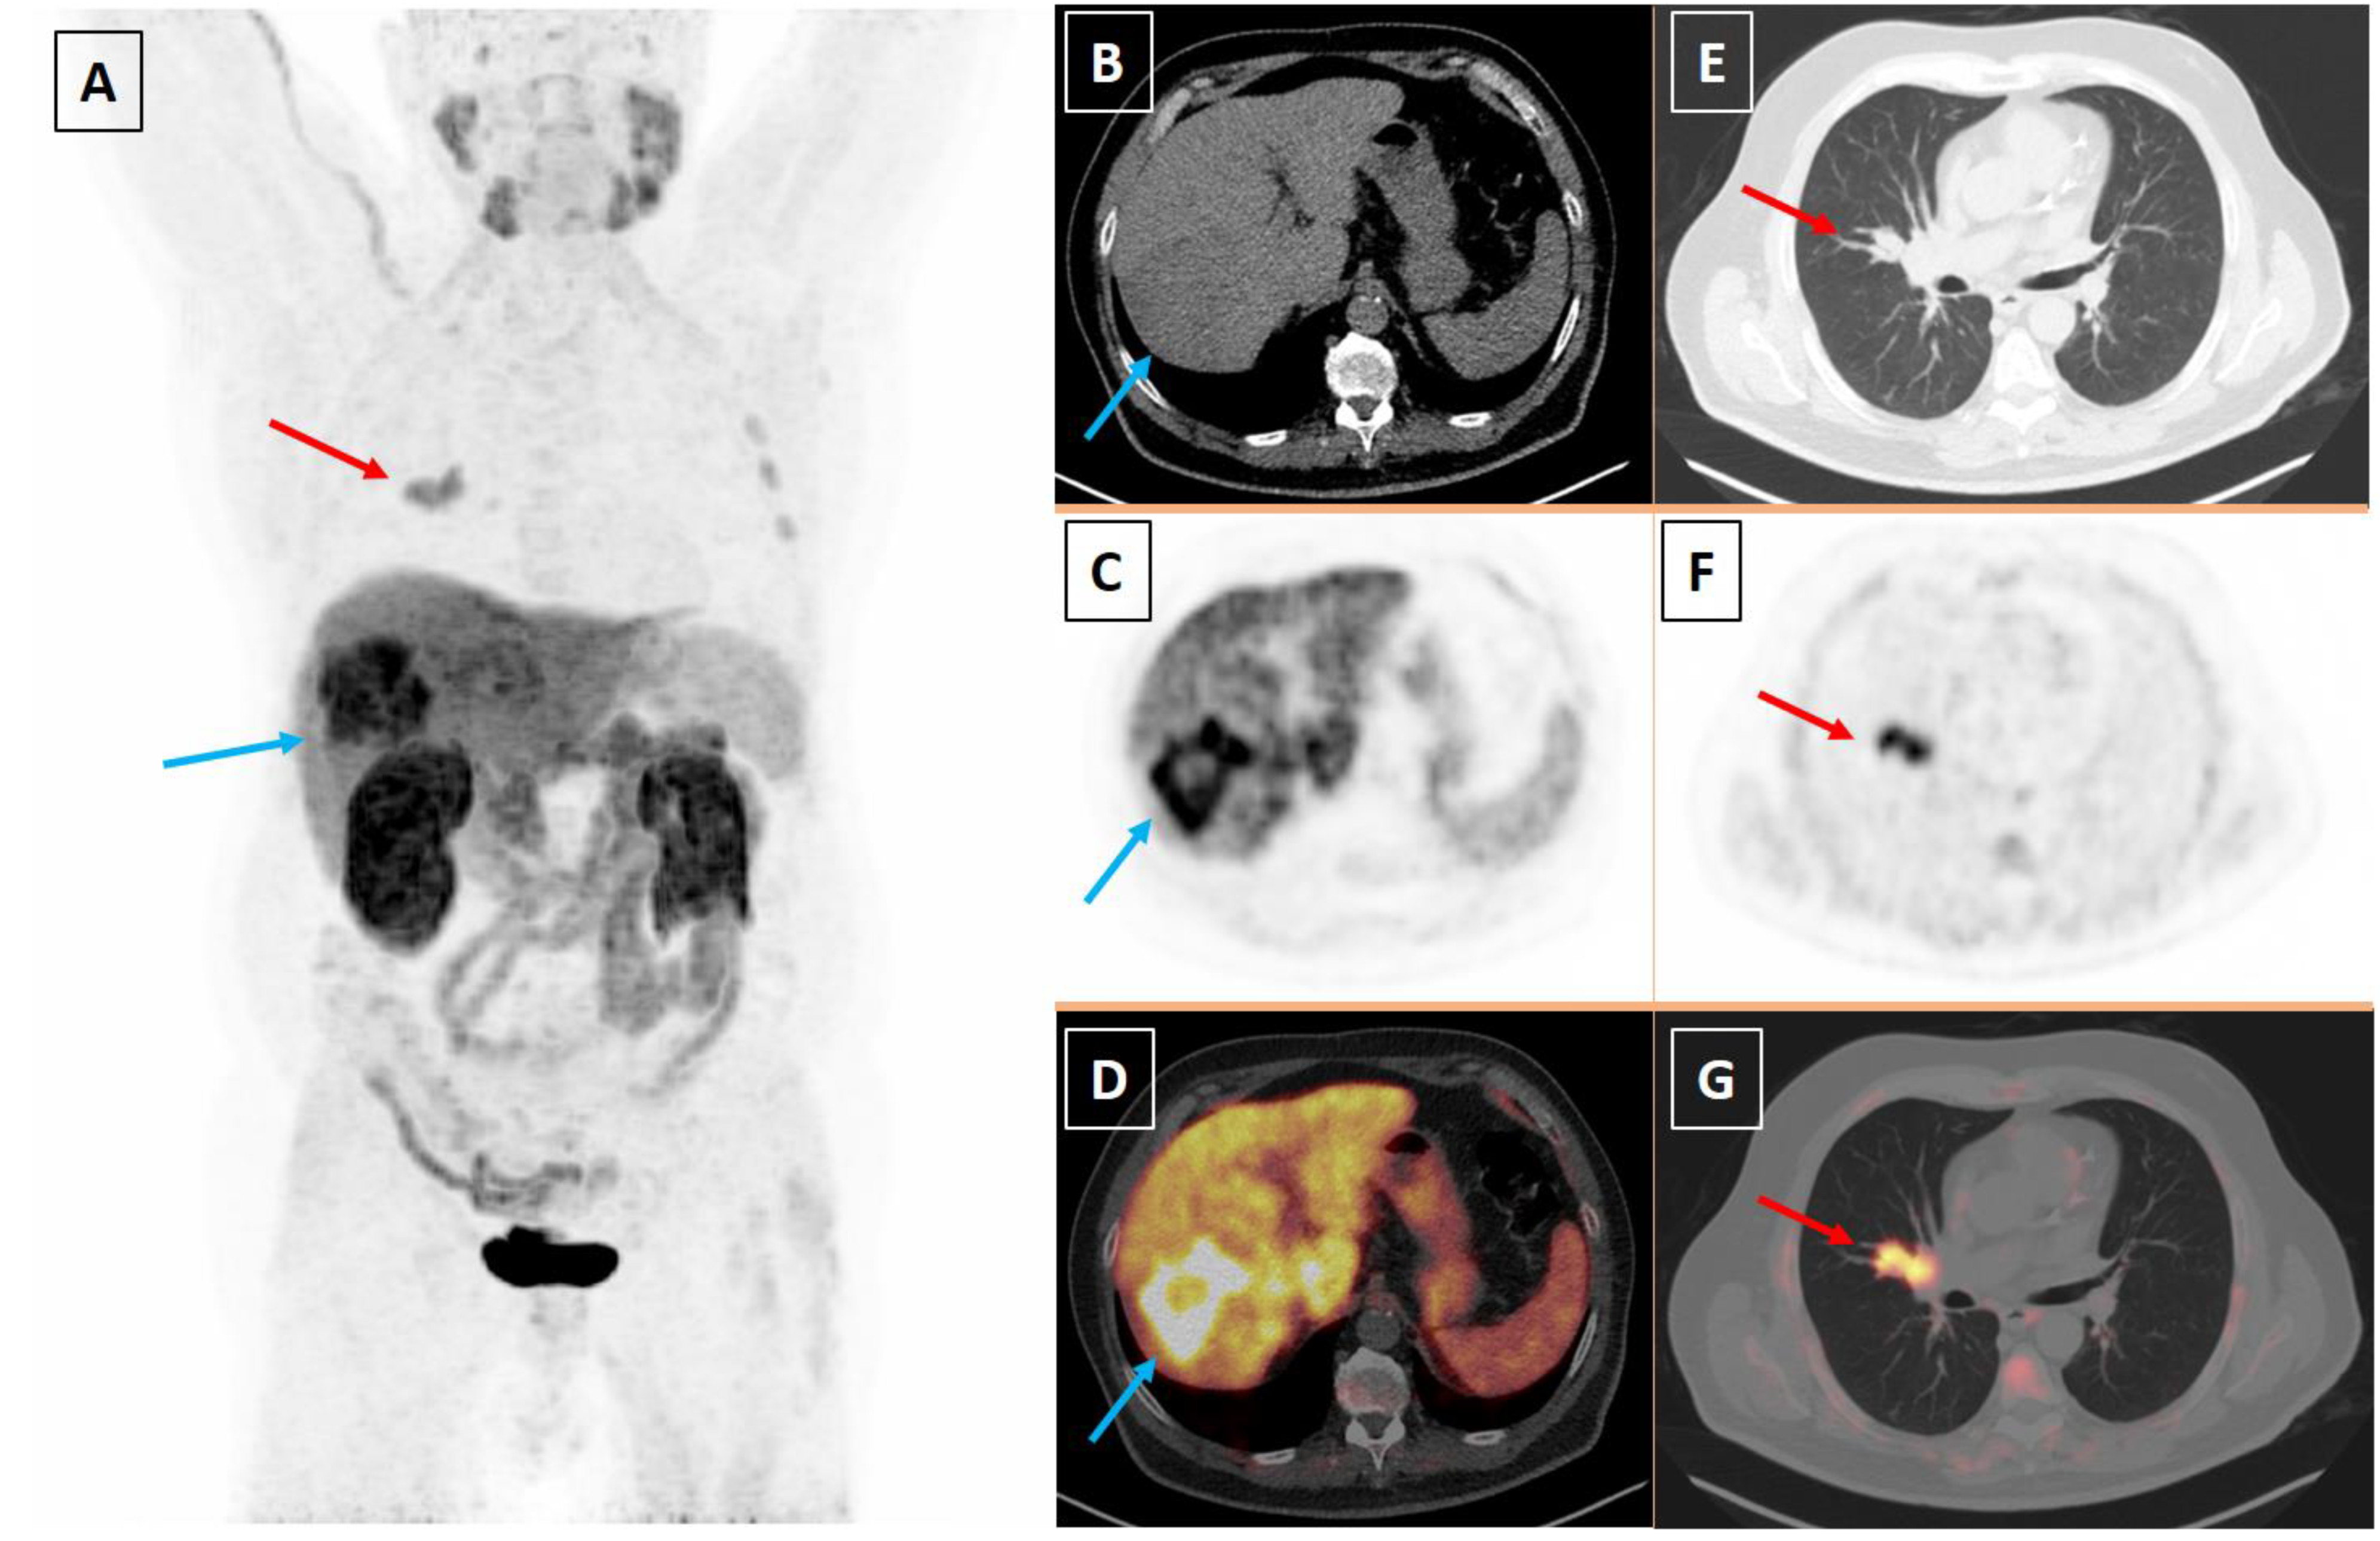

Two Birds with One Stone: Hepatocellular Carcinoma and Small Cell Lung Cancer Imaged with [18F]Fluorocholine Positron Emission Tomography/Computed Tomography

Cuzzocrea, M.; Paone, G.; Treglia, G. Two Birds with One Stone: Hepatocellular Carcinoma and Small Cell Lung Cancer Imaged with [18F]Fluorocholine Positron Emission Tomography/Computed Tomography. Diagnostics 2023, 13, 2639. https://doi.org/10.3390/diagnostics13162639